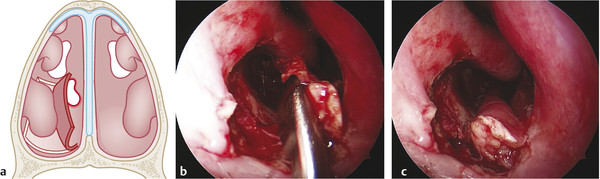

Rim and refresh the septal perforation edges with a knife until obtaining bleeding mucosal margins (Fig. 17‑5).

Suturing of the flap. Sutures (synthetic absorbable polyglycolic acid suture; 4–0) should be placed in the superior border of the flap (anteriorly and posteriorly) avoiding tension of the tissue (Fig. 17‑6).

Verify the total coverage of the septal perforation from the other nasal cavity (Fig. 17‑7).